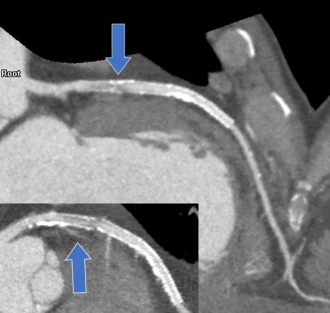

ステント内再狭窄の症例(矢印)

その後施行された冠動脈造影。ステント内再狭窄を認める(矢印)。